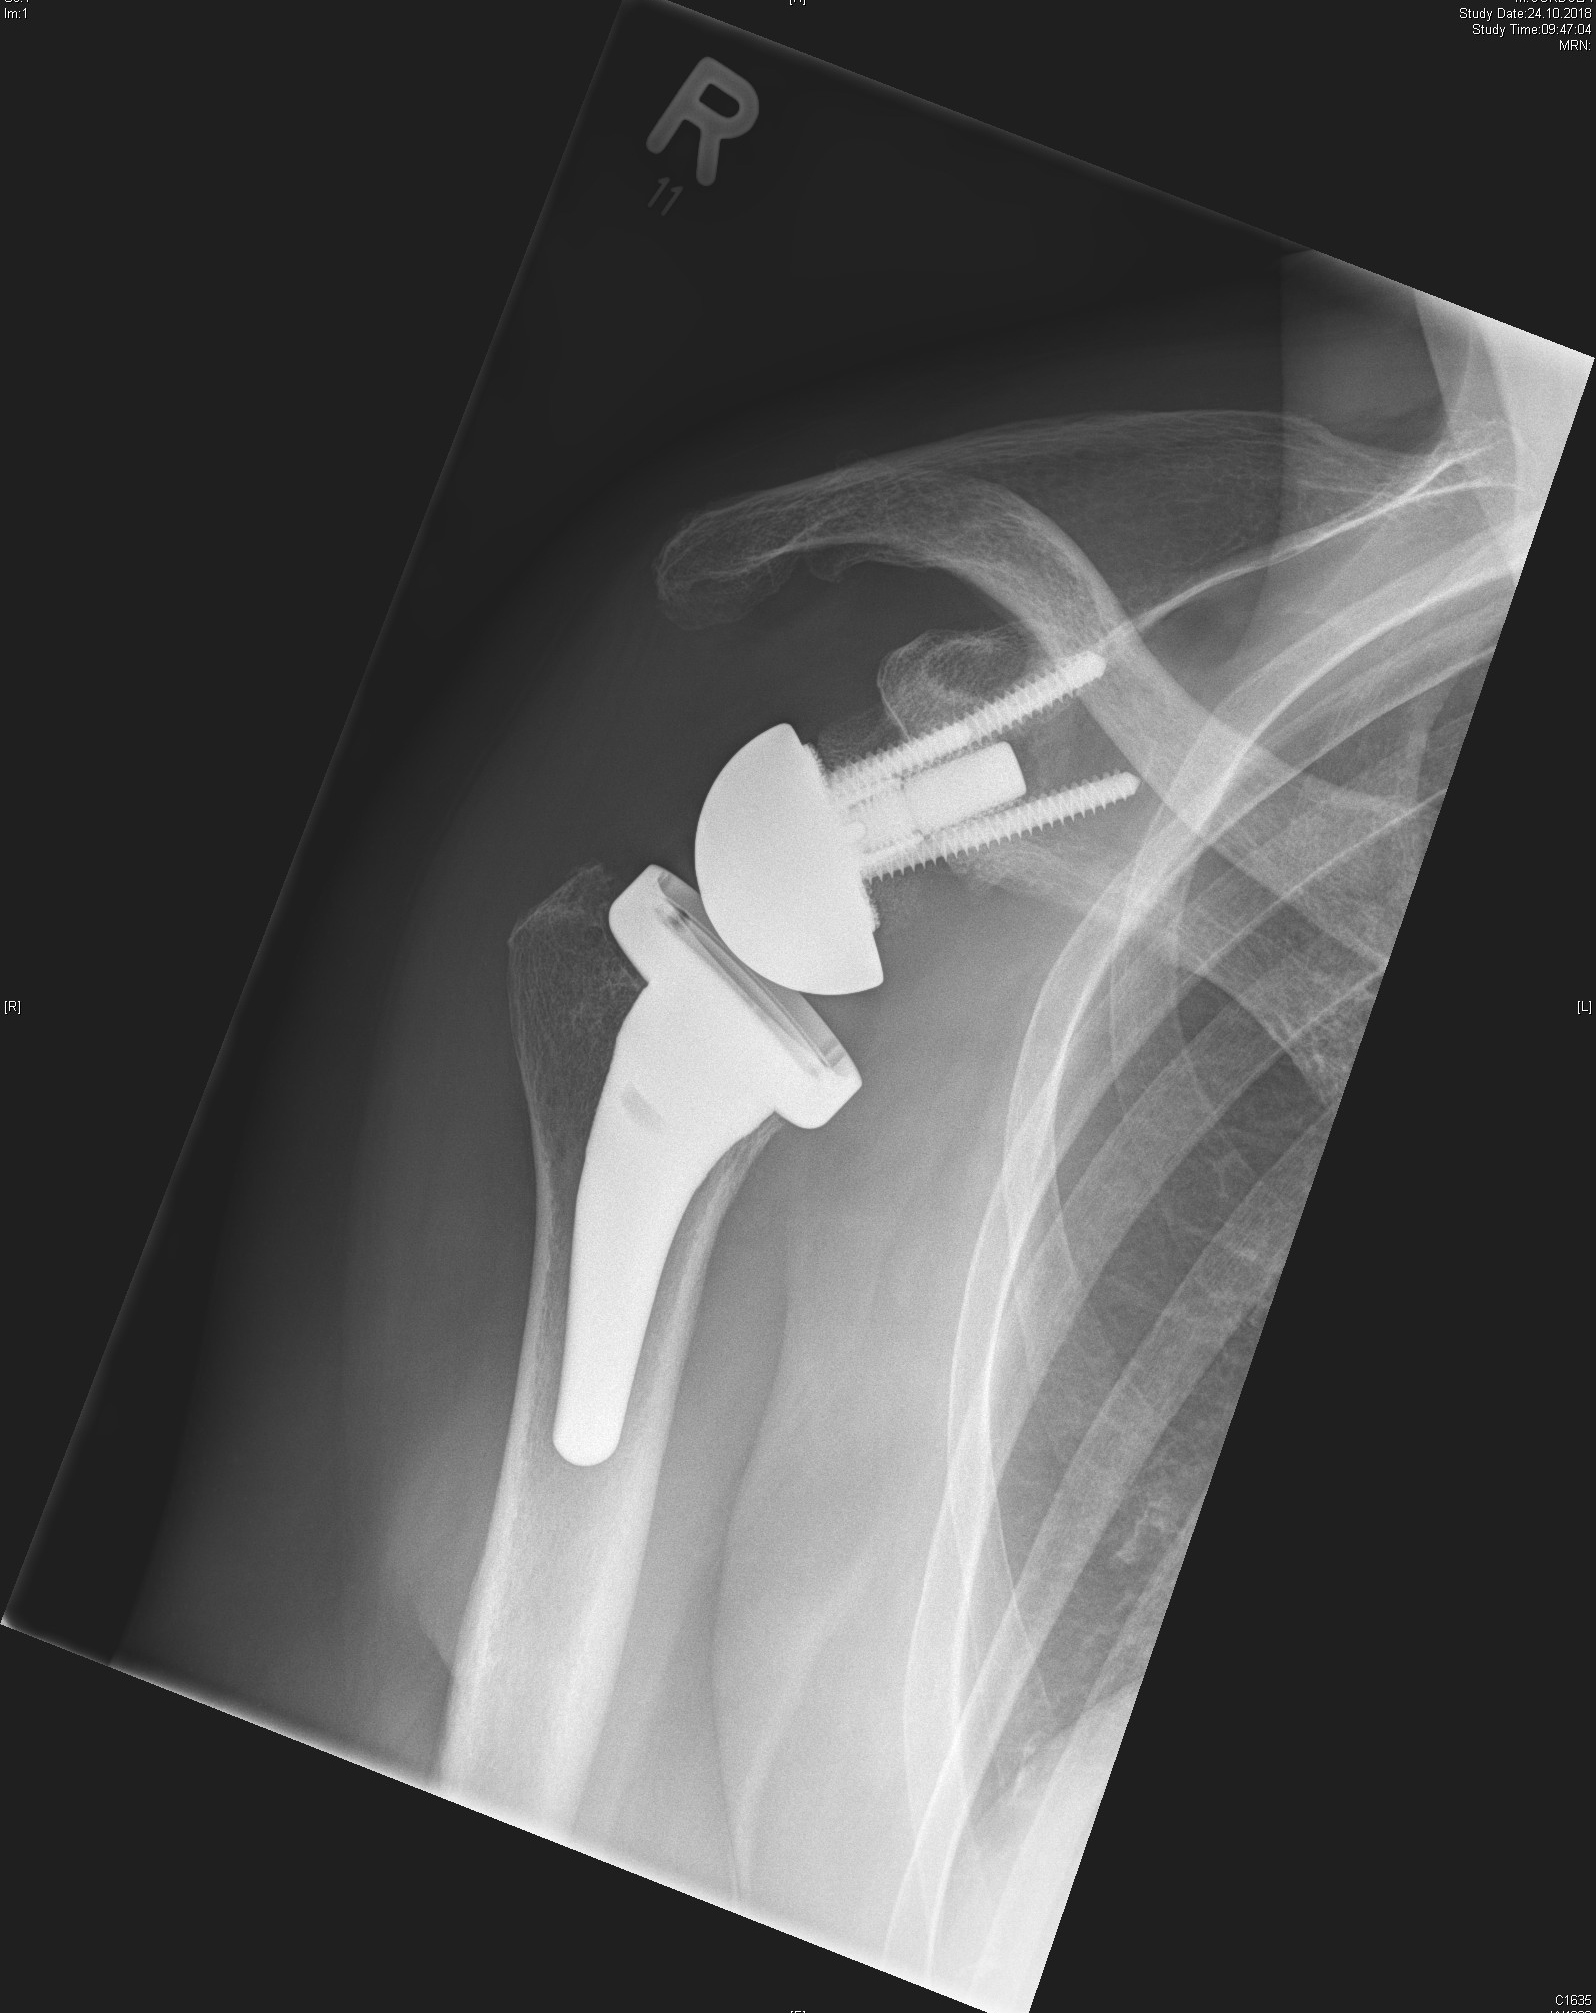

Depending on the individual situation, different types of prosthesis are used, such as the anatomical shoulder prosthesis or the inverse (reverse) prosthesis, which is particularly suitable for additional damage to the rotator cuff. In all cases, the focus is on precise diagnostics and individually tailored treatment planning.

Inverted shoulder prosthesis